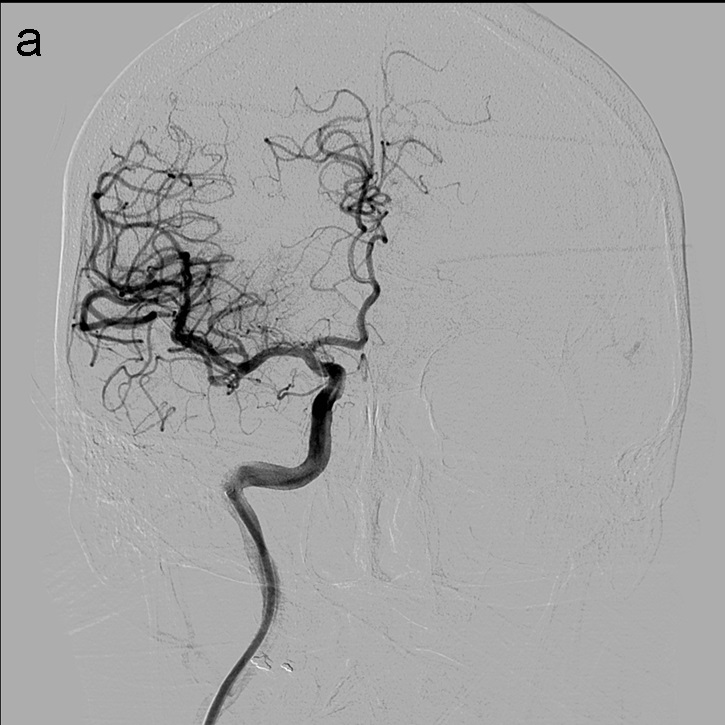

Tras la punción femoral derecha se asciende catéter balón FlowGate2 asistido por el catéter guía de asistencia punta Berenstein con guía de Terumo 0.035’’ para la cateterización de la arteria carótida común derecha y realización de estudio diagnóstico. Se obtienen series angiográficas en proyecciones anteroposterior y lateral de craneo que demuestran la presencia de trombo en el segmento M1 proximal de la ACM derecha (imagen 1). A continuación, mediante roadmap, cateterizamos la ACI derecha y realizamos un primer pase de trombectomía usando la técnica ADAPT a través del FlowGate2 con el AXS Catalyst 5 como catéter de aspiración, Trevo Pro 18 como microcatéter y con la microguía Asahi Chikai 0.014’’.

La técnica ADAPT consiste en usar el microcatéter y la microguía con el fin de facilitar la navegación del catéter de aspiración hasta aproximadamente 1-2 cm del trombo, momento en el que se retiran la microguía y el microcatéter y la llave en ‘Y’ avanzando el catéter de aspiración hasta que deja de refluír sangre por el ‘hub’. Tras esto se conecta la bomba de aspiración, se hincha el balón del FlowGate2 (imagen 2) con contraste diluido (50:50), se aspira con una jeringa de 50 cc través de éste último y se realiza el pase retirando el catéter aspiración.